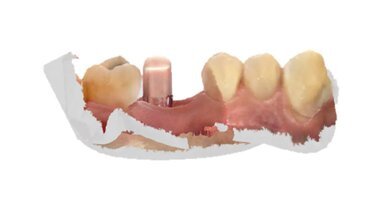

Dopo l’esecuzione dell’anestesia locale, il dente è stato rimosso e l’alveolo pulito dai residui del legamento parodontale. È stato inserito l’impianto (Zimmer TSV, Zimmer, Parsippany) 4.1 x 11,5 TSVM posizionato seguendo il protocollo consigliato dal produttore (Fig. 3). L’impianto è stato inserito a livello della cresta alveolare. È stato avvitato lo scan-abutment (Zfx Intrascan Matchholder, Zfx,). È stata rilevata un’impronta ottica intra-operatoria dell’emiarcata in cui è stato posizionato l’impianto con lo scan abutment (Fig. 3). Il gap tra l’osso vestibolare e l’impianto è stato riempito con Bio-Oss (Geistlich Pharma) (Fig. 4). Al termine della chirurgia è stato progettato e fresato il provvisorio, che è stato applicato appena pronto, dopo aver inserito la matrice in collagene volumetricamente stabile Fibro-Gide (Geistlich Pharma) precedentemente imbibita con il gel a base di polinucleotidi e acido ialuronico Regenfast (Officine Bio-Farmaceutiche Mastelli), al di sotto della vite stessa (Figg. 5, 6). Data l’accuratezza della vite non sono state necessarie suture. Al termine della procedura è stata eseguita una radiografia di controllo (Fig. 7).

Fig. 3_Scansione intra-chirurgica con scanbody.